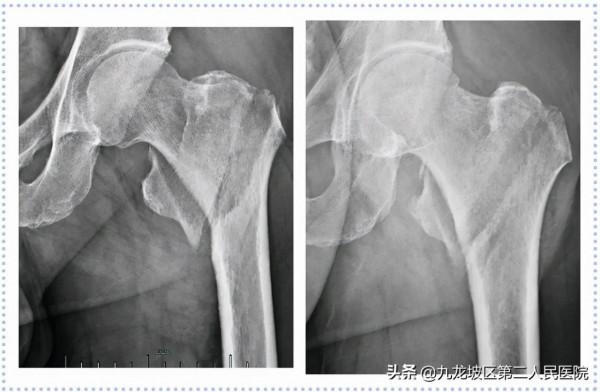

55歲女性,因“不慎跌倒致右髖部疼痛伴活動受限6小時”入院。診斷為“右股骨頸骨折(GardenⅣ型)”。2021年06月08日在我院骨科行右股骨頸動力交叉釘內固定術。

34歲女性,因“摔倒致左髖部疼痛伴活動障礙2+小時”入院。診斷為“左股骨頸骨折(GardenⅢ型)”。2021年01月15日在我院骨科行左股骨頸骨折閉合復位空心螺釘內固定術。